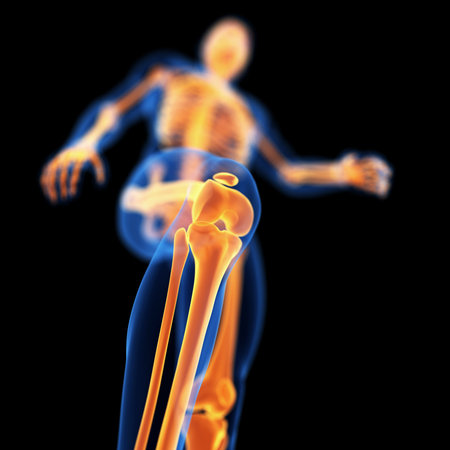

3D Illustration Human Skeleton Anatomy Bones of Tibia Fibula

Human skeleton anatomy Fibula Bone 3D Rendering For Medical Concept

Human skeleton anatomy Fibula Bone 3D Rendering For Medical Concept

Human skeleton anatomy Fibula Bone 3D Rendering For Medical Concept

3D Illustration Concept of Human Skeleton System Tibia and Fibula Bone Joints Anatomy

3d rendered medically accurate illustration of the lower leg and foot bones

Runner knee injury and pain with leg bones visible

3D Illustration Concept of Human Skeleton System Lower Limbs Bone Joints Anatomy

Human skeleton anatomy, leg bones x-ray, 3D rendering

Human body, leg , body structure , wire model